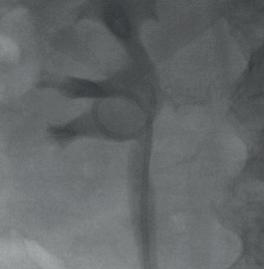

Die Photodynamische Diagnostik (PDD) verbessert die Darstellung des Tumorbereichs während der Blasenspiegelung. © Ordensklinikum Linz

Tumor im Nierenbecken als Kontrastaussparung sichtbar. Papillärer Tumor im Harnleiter (Führungsdraht ebenfalls auf dem Bild zu sehen). Papillärer, blutender Tumor im Nierenbecken (Führungsdraht auf den Bildern zu sehen).

Nierenbecken nach Tumorlaserung mit liegendem HL-Stent. © Ordensklinikum Linz

© Ordensklinikum Linz © Ordensklinikum Linz © Ordensklinikum Linz © Ordensklinikum Linz